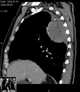

Pleural calcification

Mesothelioma is a type of cancer that develops from the thin layer of tissue that covers many of the internal organs (known as the mesothelium). The most common area affected is the lining of the lungs and chest wall. [Source: Wikipedia ]